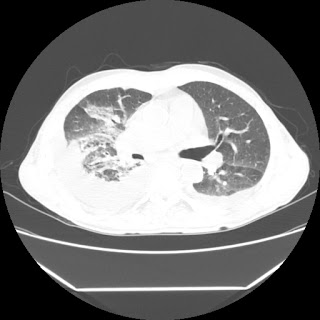

A 56 years old man with

HRCT done on summer season starting 2016